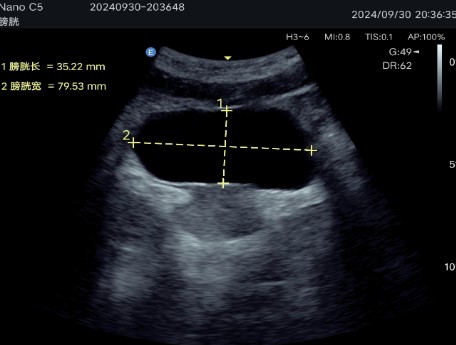

Abdominal diagnostics, obstetrics and gynecology: Allows detailed evaluation of internal organs and structures.

Multiple imaging modes: Includes B-mode, C-mode, M-mode and Pulsed Doppler (PW), ensuring precise visualizations for various clinical applications.

Maximum scanning depth: 0-10 cm